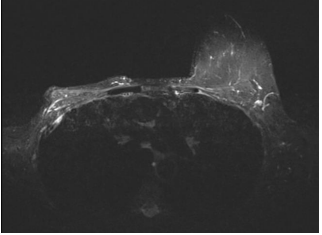

According to European Standard Operating Procedures on Electrochemotherapy (ESOPE) guidelines, ECT was performed with bleomycin intralesional. Three electrodes were introduced in intercostal space with CT scan imaging guide. International units (IU) of bleomycin were introduced in the lesion. After the intralesional chemotherapy administration three electrodes were introduced and needles extruded to penetrate the whole lesion so that the electric field could cover the entire volume of it. The entire procedure lasted 20 minutes, and a sample of the lesion was taken for histological confirmation. The patient was hospitalized for 2 days receiving antibiotic prophylaxis with cephalosporins.Procedure was well tolerated, without side effects. The histological examination confirmed the presence of single Metastasis originating from the previous carcinoma of the breast.Thoracic HRTC was performed one day after ECT treatment and no signs of lung damage were found. Thoracic HRTC performed one month after the procedure showed downstaging of the lesions (Figure 4).

Figure 4: Thoracic Hight Resolution Computed Tomography (HRCT) image.

Lesion necrotic pattern (January, 2022).